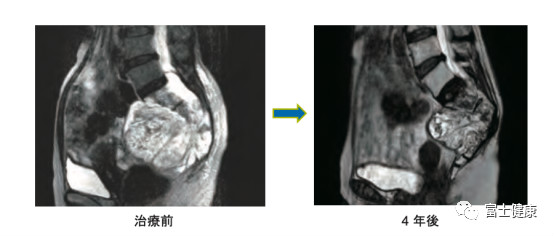

1.2.1對放射線抵抗性癌癥具有療效 如上所述,重離子線在體內(nèi)形成布拉格峰,在相應(yīng)部位產(chǎn)生高密度電離效應(yīng)。高密度電離除了產(chǎn)生的生物效果(細(xì)胞殺死作用)比質(zhì)子線和X線更療效大以外還有其他重要的:癌癥中,因細(xì)胞處于低氧環(huán)境下等原因,而存在有對X線和質(zhì)子線治療抵抗的難治性癌癥。重離子線治療對這些難治性癌癥的療效值得期待。放射線抵抗癌中代表性的癌癥如圖4所示的骨軟組織腫瘤和腺癌類腫瘤,這兩種癌癥的重離子治療在日本都在國民醫(yī)療保險涵蓋范圍之內(nèi)。

圖4.骶骨脊索瘤一例